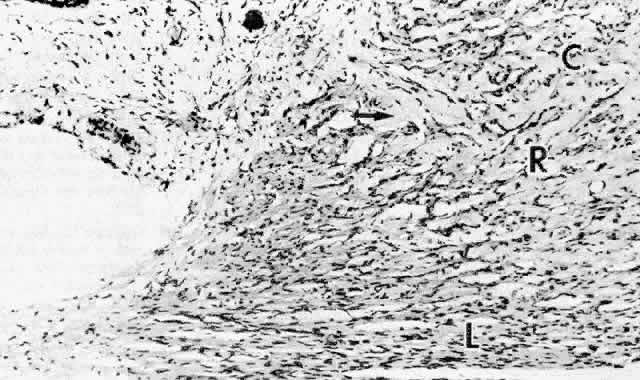

The ciliary muscle has a complex architecture, and its three dimensional organization and function have been difficult to visualize. Traditionally, the muscle is divided into three portions (Fig. 34): an outer longitudinal or meridional portion ( Brücke's muscle), a middle oblique portion (also called reticular or radial), and an inner circular component ( Müller's muscle). These regions are so interconnected that they were recognized early as designed to function like a single muscle mass when stimulated.37 Experimental evidence in humans, primates, and other mammals supports the view that the contracting ciliary muscle undergoes a shortening with anterior traction on the ora serrata region, and an inward and posterior pull on the scleral spur and trabeculum.6,38–40 Contraction of the oblique and circular portions in particular contributes a strong anterior and inward movement of the processes. The result is a well coordinated anterior-inward squeezing effect, displacing the processes toward the lens equator, and resulting in relaxation of zonular pull on the lens capsule. This inward movement of the ciliary processes has been dramatically shown by cinematography in primates after iridectomy.41

Fig. 34. Ciliary muscle showing circular (C), radial (R), and longitudinal (L) divisions and their relation to the scleral spur (ss) at age 2. A rare muscle bundle is present in the iris root. (hematoxylin-eosin, X 250)

Several investigators have used somewhat different schemata based on muscle dissection to illustrate the ciliary muscle fiber topography that allows such a complex yet coordinated muscle movement. The muscle fibers are visualized as each arising by two heads in interdigitating V patterns (Fig. 35).37,42,43 The two heads are close together in the longitudinal muscle so the fibers pass in an almost straight anteroposterior direction. For the oblique muscle fibers, the angle between the two heads is wider and for the circular muscle fibers is obtuse, allowing the latter to function in an almost purely circular plane.

Fig. 35. Diagram of ciliary muscle divisions: circular (C), radial (R), and longitudinal (L). Anterior attachments to the collagenous scleral spur (SP) and the trabecular beams are indicated. SC, Schlemm's canal. (Modified from Hogan MJ, Alvarado JA, Weddell JE: Histology of the Human Eye. Philadelphia, WB Saunders, 1971; and Rohen JW: Der Ziliarkorper als functionelles System. Morph Jahrbuch 92:415, 1952)

The great bulk of the ciliary muscle lies in the anterior two thirds of the ciliary body (see Fig. 5). At the light microscopic level in the child, the longitudinal muscle shows a primary attachment to the scleral spur and to the outer corneoscleral and uveal trabecular meshwork, while the oblique radial fibers have more connection to the inner uveal meshwork (see Fig. 34). The circular muscle attachments are primarily to the adjacent ciliary and iris root stroma. During aging the addition of significant fibrous tissue and hyaline greatly increases the bulk of the radial and circular muscles (Fig. 36) but not the longitudinal muscle. Tamm, Tamm, and Rohen44 found that connective tissue comprised about half of the oblique muscle in the 50- to 60-year-old age group. The circular muscle was also significantly increased in area and partially separated from the oblique muscle by this connective tissue, which was continuous with hyaline in the processes. The overall effect of aging on the ciliary muscle made it shorter in length and greater in area with a prominence of the circular muscle, resulting in a forward and inward configuration resembling the accommodated state. Others have described some atrophy of the muscle with decreased nuclei, particularly in the circular muscle and over the age of 40 years.45

Fig. 36. Dense pale hyaline deposition (arrow) between the circular (C) and radial (R) but not the longitudinal (L) muscle bundles of a 64-year-old patient. Compare with Figure 34 from 2-year-old child. (hematoxylin-eosin, X 250)